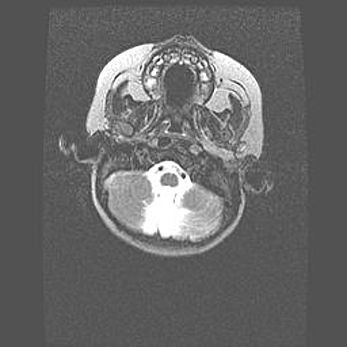

Наружная гидроцефалия с возможной атрофией височных областей.

Возраст: 28 дней

Вес: 3670 г

Пол: мужской

Окружность головы: 38 см

Срок гестации: 40 недель

Гидроцефалия головного мозга у новорожденных – это заболевание, которое характеризуется скоплением избыточного количества спинномозговой жидкости в желудочковой системе головного мозга в результате затруднения её перемещения от места выработки к месту поглощения в кровеносную систему или вследствие нарушения абсорбции. При открытой наружной форме гидроцефалии у новорожденных расширяются и переполняются субарахноидные пространства.

При нормотензивных  формах,  которые,  как  правило,  являются  следствием  перенесенных ишемических  повреждений  паренхимы  мозга,  возможно  сочетание микроцефалии  с нормотензивной гидроцефалией. В основе данных изменений лежит атрофия больших полушарий с преимущественной  локализацией  в  лобно-височных  областях.